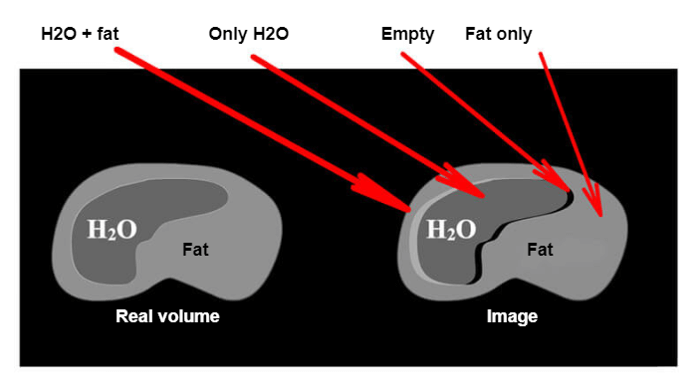

The difference in the rotation speed of the Hydrogen protons of water and fat is always 3.4 ppm. This means that for a magnetic field of 1.5 T, the difference is 208 Hz. We have seen that the signal was moved by Fourier Transformation by its frequency. Because of this difference in the rotational speed of the water protons relative to those of fat, they will be artificially shifted against each other.

If this 208 Hz are shown in more pixels, then these signals will be located in the wrong position. Notice that around the organ, there will be a part where the signals of water and fat will add up (H2O + fat = white stripe), a part where there is no organ (H2O = normal signal the organ), and a part with no signal (nothing = black band). This is the chemical shift.

Bandwidth and Chemical Shift

The bandwidth represents the different frequencies contained in the signal. These frequencies cover all the FOV and are distributed according to the frequency matrix. Based on the manufacturer, the bandwidth can be adjusted according to the variation of both sides of the center, The number of Hz per pixel or the number of pixels covered by the chemical shift.